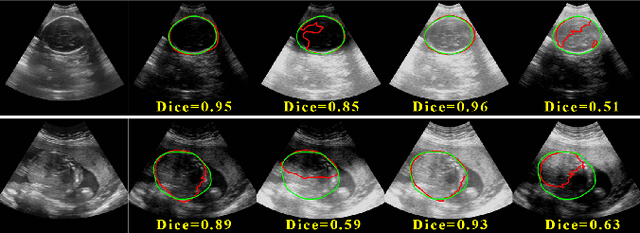

Deep Neural Networks (DNNs) suffer from the performance degradation when image appearance shift occurs, especially in ultrasound (US) image segmentation. In this paper, we propose a novel and intuitive framework to remove the appearance shift, and hence improve the generalization ability of DNNs. Our work has three highlights. First, we follow the spirit of universal style transfer to remove appearance shifts, which was not explored before for US images. Without sacrificing image structure details, it enables the arbitrary style-content transfer. Second, accelerated with Adaptive Instance Normalization block, our framework achieved real-time speed required in the clinical US scanning. Third, an efficient and effective style image selection strategy is proposed to ensure the target-style US image and testing content US image properly match each other. Experiments on two large US datasets demonstrate that our methods are superior to state-of-the-art methods on making DNNs robust against various appearance shifts.